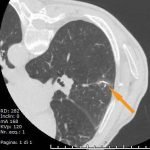

Con guida radiologica (raggi X, ecografia, TC) è possibile posizionare un marker nel contesto di un piccolo nodulo. Questo ha una estremità che affiora dalla cute, per cui il Chirurgo una volta ispezionata la zona da operare, seguendo questa traccia è facilitato nel raggiungere la sede desiderata.

Questa è una tecnica molto usata in senologia e nella rimozione di piccoli noduli polmonari o sottocutanei, retroperitoneali, etc.